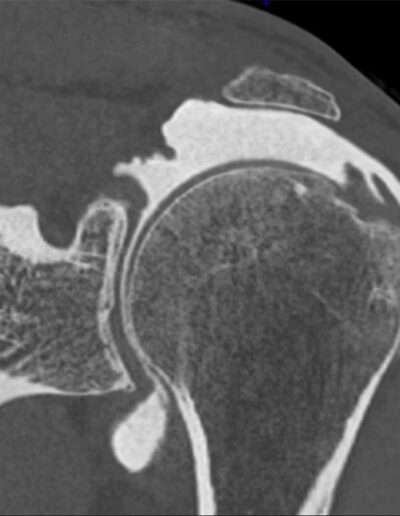

Shoulder Left

Patient 45 y/o, Male, right-handed

• 2003: Open surgery for AC joint dislocation (Dr. Elsewhere)

• 10/2024: Rotator cuff repair (Dr. Thibault LAFOSSE)

• Pain and instability 3 months postoperative, triggered by carrying a bag